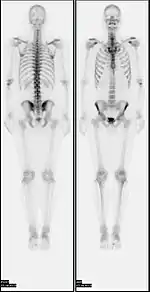

In a typical bone scan technique, the patient is injected (usually into a vein in the arm or hand, occasionally the foot) with up to 740 MBq of technetium-99m-MDP and then scanned with a gamma camera, which captures planar anterior and posterior or single photon emission computed tomography (SPECT) images.[19][14] In order to view small lesions SPECT imaging technique may be preferred over planar scintigraphy.[20]

In a single phase protocol (skeletal imaging alone), which will primarily highlight osteoblasts, images are usually acquired 2–5 hours after the injection (after four hours 50–60% of the activity will be fixed to bones).[19][14][21] A two or three phase protocol utilises additional scans at different points after the injection to obtain additional diagnostic information. A dynamic (i.e. multiple acquired frames) study immediately after the injection captures perfusion information.[21][22] A second phase "blood pool" image following the perfusion (if carried out in a three phase technique) can help to diagnose inflammatory conditions or problems of blood supply.[23]